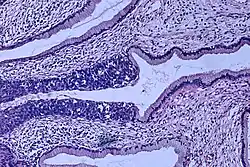

Cervical intraepithelial neoplasia (CIN) means the development of abnormal cells on the surface of the cervix. HPV infections cause CIN, but in most cases, it is resolved by the immune system. However, a small percentage of people might develop a more serious CIN, which, if left untreated, can develop into cervical cancer.[66][67] CIN is often diagnosed during routine Pap smear examination or colposcopy.[67]

The naming and histologic classification of cervical carcinoma precursor lesions has changed many times over the 20th century. The World Health Organization classification system was descriptive of the lesions, naming them mild, moderate, or severe dysplasia or carcinoma in situ (CIS).[68][69] The term cervical intraepithelial neoplasia (CIN) was developed to place emphasis on the spectrum of abnormality in these lesions and to help standardize treatment.[69] For premalignant dysplastic changes, cervical intraepithelial neoplasia grading (CIN 1–3) is used. It classifies mild dysplasia as CIN1, moderate dysplasia as CIN2, and severe dysplasia and CIS as CIN3.[70] More recently, CIN2 and CIN3 have been combined into CIN2/3. These results are what a pathologist might report from a biopsy.